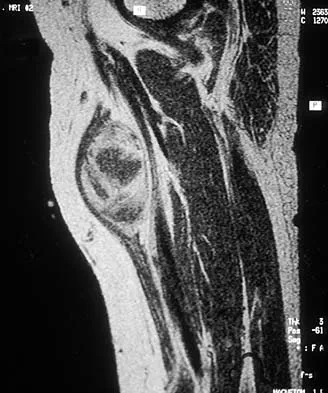

A 43-year-old woman has had pain in the left hip for the past 2 months. A radiograph, CT scan, MRI scan, and biopsy specimens are shown in Figures 16a through 16e. What is the most likely diagnosis?